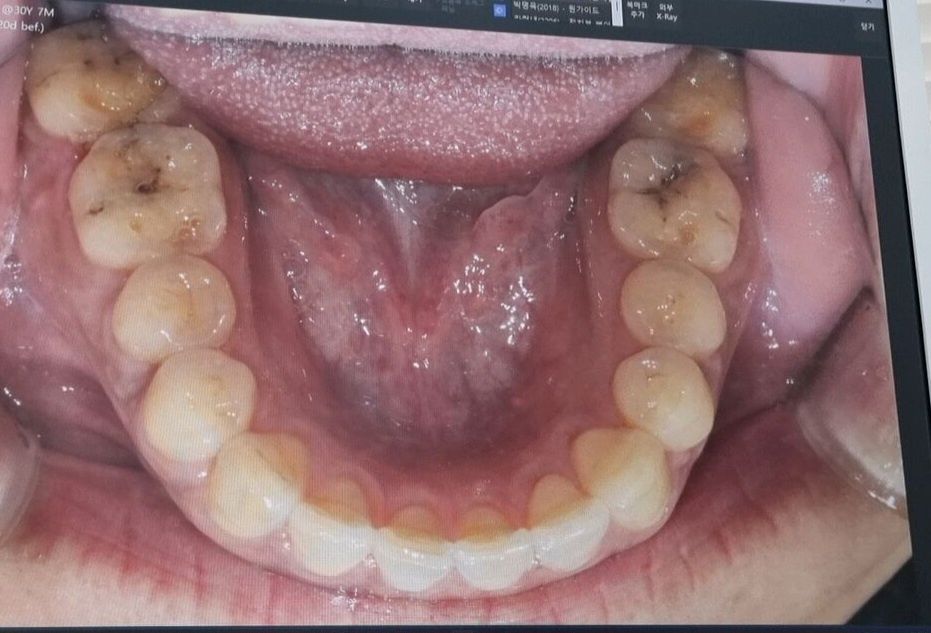

이갈이 치아 마모 및 충치 크라운치료 필요 여부

얼마 전 A치과 방문하여 위아래 어금니 7개 크라운 소견 받았습니다.

충치 및 이갈이로 인한 치아 파절 마모입니다.

진료 시작하여 신경치료는 하지 않고 오른쪽 치아 4개 크라운 완료한 상태에서,

치아 사진 첨부하였습니다.